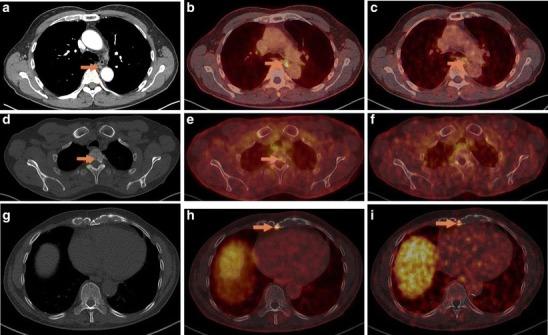

In 14 selected patients with PSA relapse of prostate cancer, [(18)F]DCFPyL PET/X-ray computed tomography (CT) was performed in addition to [(68)Ga]Ga-PSMA-HBED-CC PET/CT. A systematic comparison was carried out between results obtained with both tracers with regard to the number of detected PSMA-positive lesions, the standardized uptake value (SUV)max and the lesion to background ratios.

RESULTS

All suspicious lesions identified by [(68)Ga]Ga-PSMA-HBED-CC were also detected with [(18)F]DCFPyL. In three patients, additional lesions were observed using [(18)F]DCFPyL PET/CT. The mean SUVmax in the concordant [(18)F]DCFPyL PSMA-positive lesions was significantly higher as compared to [(68)Ga]Ga-PSMA-HBED-CC (14.5 vs. 12.2, p = 0.028, n = 15). The mean tumor to background ratios (n = 15) were significantly higher for [(18)F]DCFPyL compared to [(68)Ga]Ga-PSMA-HBED-CC using kidney, spleen, or parotid as reference organs (p = 0.006, p = 0.002, p = 0.008), but no significant differences were found using the liver (p = 0.167) or the mediastinum (p = 0.363) as reference organs.

在14例选定的前列腺癌PSA复发患者中,除了进行[(68)Ga]Ga-PSMA-HBED-CC PET/CT外,还进行了[(18)F]DCFPyL PET/X射线计算机断层扫描(CT)。对两种示踪剂获得的结果在检测到的PSMA阳性病变数量、标准化摄取值(SUV)最大值和病变与背景比值方面进行了系统比较。

结果

[(68)Ga]Ga-PSMA-HBED-CC识别出的所有可疑病变也能用[(18)F]DCFPyL检测到。在3例患者中,使用[(1)F]DCFPyL PET/CT观察到了额外的病变。与[(68)Ga]Ga-PSMA-HBED-CC相比,[(18)F]DCFPyL PSMA阳性病变中的平均SUV最大值显著更高(14.5对12.2,p = 0.028,n = 15)。以肾脏、脾脏或腮腺作为参考器官时,[(18)F]DCFPyL的平均肿瘤与背景比值(n = 15)显著高于[(68)Ga]Ga-PSMA-HBED-CC(p = 0.006,p = 0.002,p = 0.008),但以肝脏(p = 0.167)或纵隔(p = 0.363)作为参考器官时未发现显著差异。